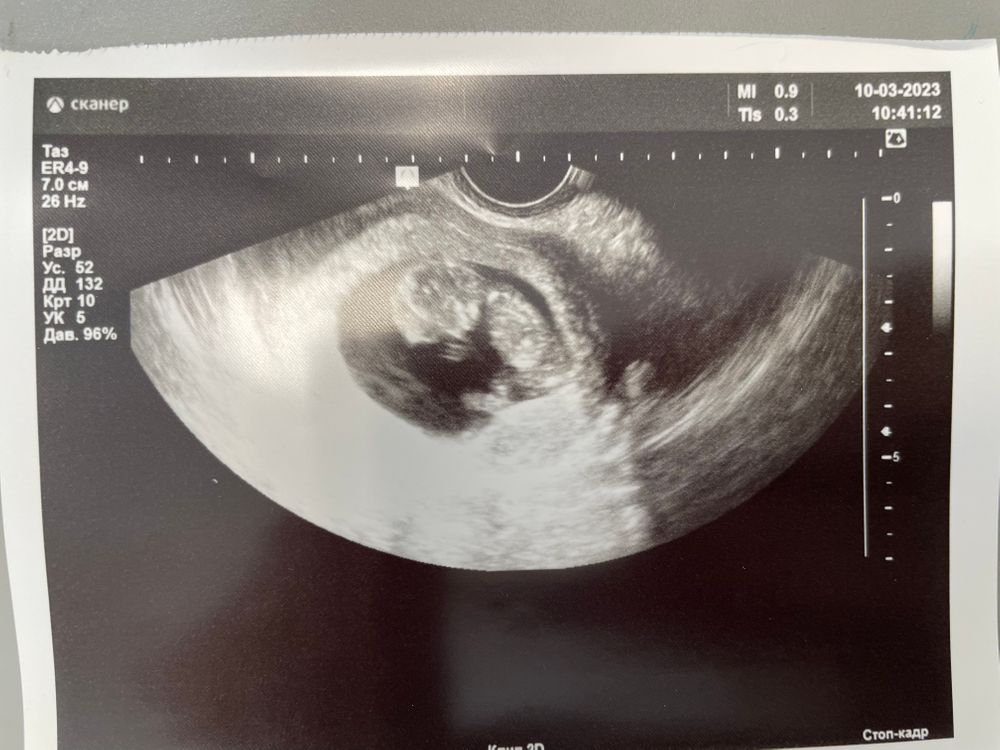

Кира, теперь надо как то до скрининга дожить🤦🏻‍♀️. Малышок 3.8см, такой маленький а уже машет и ручками и ножками.

Кира, да не говори, я сестре звоню, говорю ручками машет, она говорит ты что, он же маленький, у него еще ничего нет))) узи на сроке 10,6 акушерский, по узи 10,4